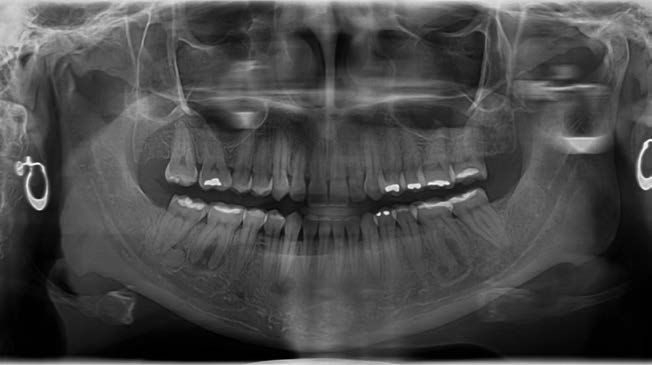

En una radiografía panorámica del año 2018 (Figura 1) se observaron lesiones difusas en la mandíbula, localizadas en las regiones periapicales de los dientes 36, 43, 46 y 47. Estas lesiones presentaban un predominio de áreas radiotransparentes, con la presencia de pequeñas zonas de material radiodenso.